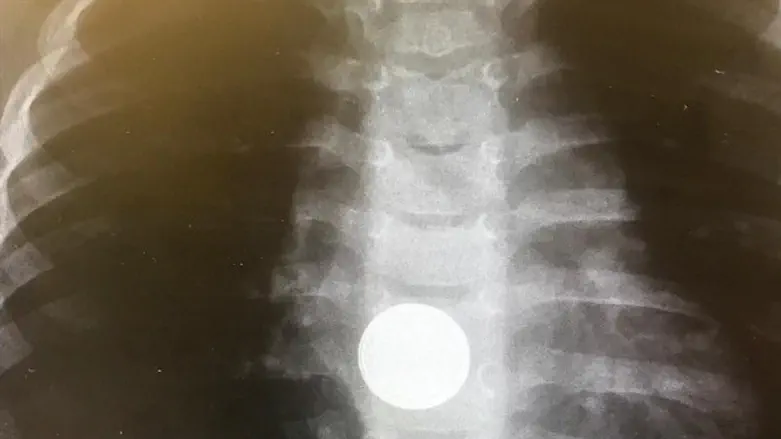

About a month ago, a child arrived at Shaare Zedek Medical Center, a 3-year-old girl whose parents suspected she had swallowed an object. A quick x-ray taken in the emergency room showed the girl had swallowed a large battery that stuck in her esophagus and endangered her life.

In an emergency intervention by the Gastro Children's team, the battery was removed endoscopically. However, the battery, which was only two hours in the esophagus from the time of ingestion, had already caused her child severe esophageal burns that required multidisciplinary involvement by pediatric gastroenterologists, dermatologists, ear-nose-throat doctors, and chest surgeons. The girl received comprehensive treatment and after a month's hospitalization, was released home in good health.